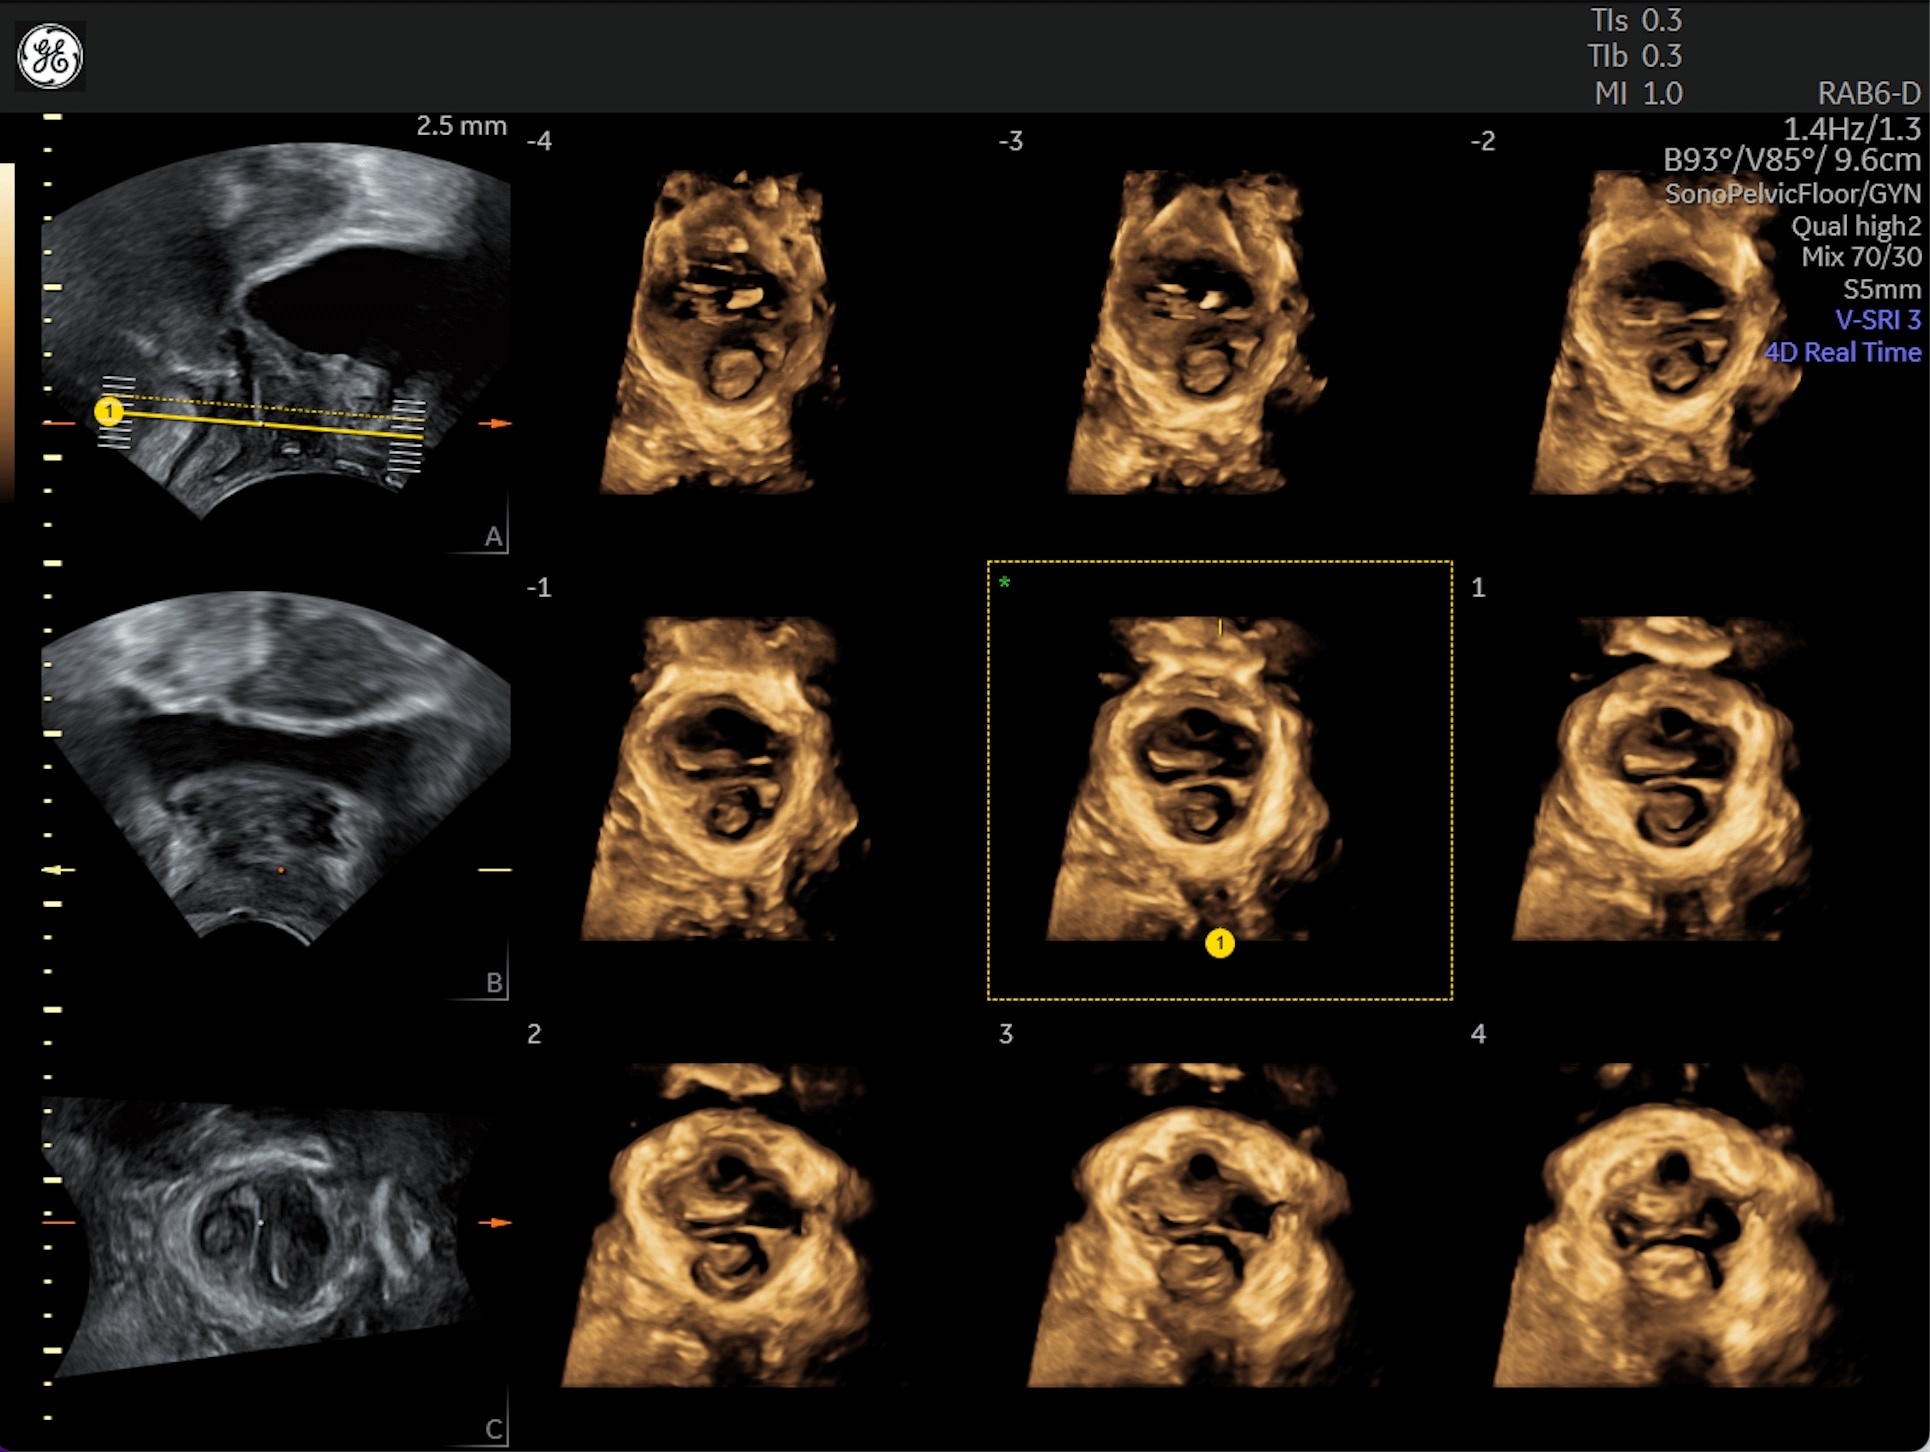

Generate spectacular 2D/3D and color Doppler images with increased penetration and stunning clarity, to help visualize critical details needed for diagnostic assurance. The Lyric Architecture unlocks new imaging and processing power to expand your imaging capabilities for years to come